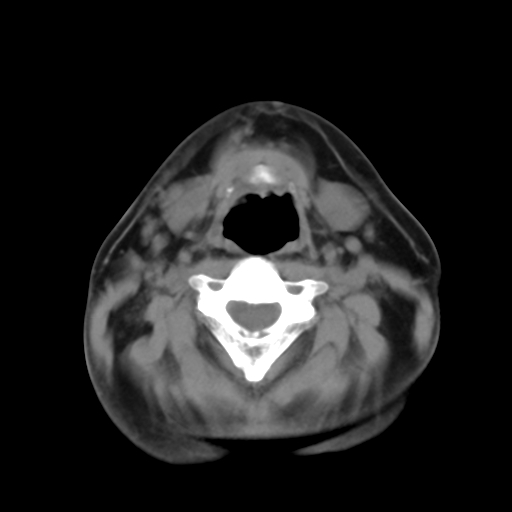

标题: CT24019:男,45岁,发现颈部肿物5个月。 [打印本页]

男,45岁,发现颈部肿物5个月,彩超示:双侧颈部及下颌部软组织增厚。

考虑双侧颈项部良性对称性脂肪增多症。